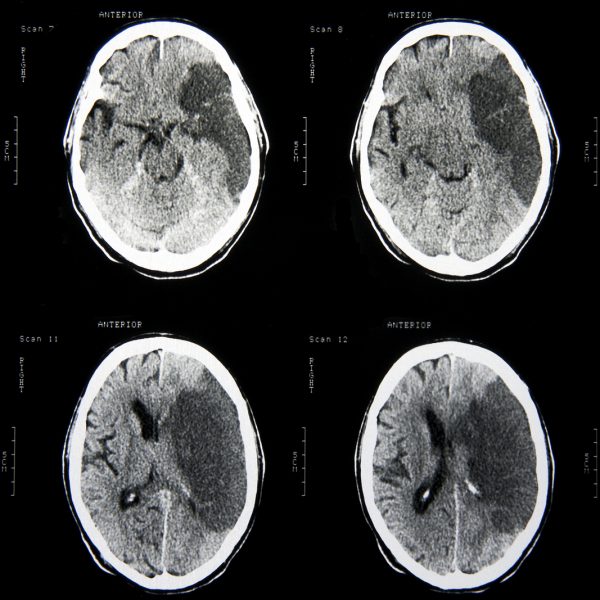

Харвалтыг хэрхэн оношлох вэ?

Тархины цус харвалт гэж юу вэ?